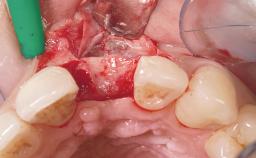

Immediate Flapless Placement of an Implant in a Maxillary Left Central Incisor Site

A 42-year-old female patient was referred to our clinic at the School of Dentistry of the University of São Paulo in November 2004, presenting a deficient restoration in the upper left central incisor. The clinical examination revealed no gingival retraction or any signs of gingival inflammation and, therefore, previous periodontal treatment was not considered. The patient presented a high lip line at full smile and a thin tissue biotype. This combination characterized a high-risk situation from an anatomic point of view, which required careful preoperative planning and cautious surgical execution.

Soft Tissue Grafting None

Soft Tissue Anatomy Intact Defective

Soft Tissue Contour and Volume Ideal